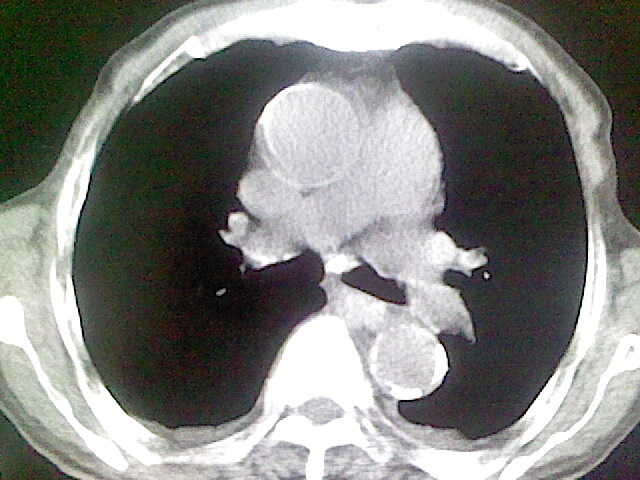

以下是引用zsl6918在2008-8-28 16:49:00的发言:[br]双肺炎性病灶,食管狭窄估计与心房增大压迫所致。

以下是引用xulianj在2008-8-28 20:36:00的发言:[br]慢支肺气肿伴感染,右上肺陈旧性结核;食道建议胃镜检查。

以下是引用wqs571018在2008-8-28 21:18:00的发言:[br]慢支继发感染,右上肺陈旧性结核;食道建议胃镜检查。